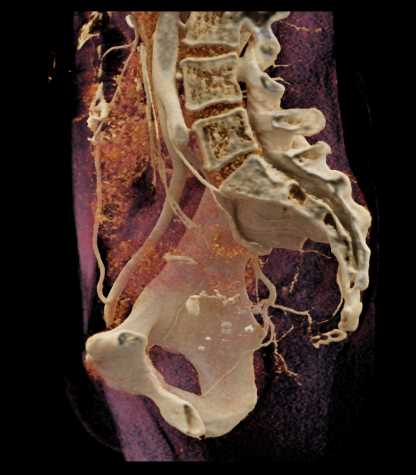

Urachal Carcinoma of the Bladder